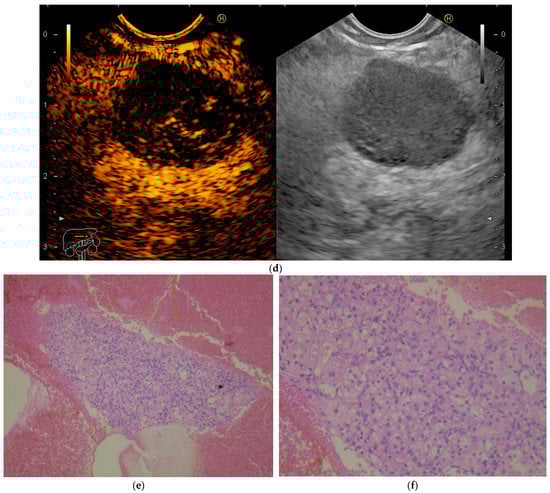

A 54-year-old male ex-smoker was referred by the oncologist for evaluation of a pancreatic mass. Personal medical history was remarkable for left nephrectomy and adrenalectomy 6 months before, for RCC. Follow-up imaging—computed tomography and magnetic resonance imaging—revealed a 16/18 mm pancreatic mass suggestive of a neuroendocrine tumor. He had no digestive complaints. Physical examination was unremarkable, except for a post-operative left flank scar. Laboratory work-up showed mild normocytic anemia. Tumor markers (CEA, CA 19-9, CA 125), serum chromogranin, serotonin and urinary 5-hydroxyindoleacetic acid were within normal limits. We performed endoscopic ultrasound (EUS) to further characterize the pancreatic mass and obtain a histopathologic diagnosis. EUS showed a well-delineated, round hypoechoic lesion in the pancreatic isthmus (Figure 1a), with a hard homogeneous pattern on elastography (Figure 1b). Upon administration of contrast media (SonoVue), rapid uptake of contrast was seen in the arterial phase, with washout in the late phase (Figure 1c,d). A fine-needle biopsy (FNB) was performed using a 20 G ProCore needle, and the histopathology report confirmed the diagnosis of metastatic RCC in the pancreas (Figure 1e,f). Following the oncology board’s decision, the patient was referred for surgery. No recurrence of metastatic lesions was found on imaging at the one-year follow-up.

(a) Endoscopic ultrasound using a linear probe: hypoechoic mass in the isthmus of the pancreas. (b) Real-time elastography showing a hard homogeneous pattern in the lesion. (c) Contrast-enhanced EUS showing a hyperenhancing pattern of the lesion in the arterial phase. (d) Contrast-enhanced EUS image showing washout of the lesion in the late phase. (e,f)—Hematoxylin-eosin stain, 100× and 200× magnitude, showing RCC tumor proliferation.

A 68-year-old dialysis patient presented for further evaluation of a pancreatic mass detected on ultrasound and confirmed by CT scan. He was complaining of postprandial bloating but had overall good performance status. Three years before the presentation, the patient had undergone right nephrectomy for Grawitz tumor and was currently undergoing dialysis. Laboratory workup showed considerably decreased glomerular filtration rate and mild normocytic anemia, with no other specific findings. Tumor markers (CEA, CA 19-9, CA 125) were within normal limits. EUS revealed a 25 mm cephalopancreatic mass (Figure 3) with a hard homogeneous pattern on elastography and a hyperenhancing pattern on contrast administration (SonoVue). Transduodenal FNB with a 20G needle confirmed the mass to be an RCC metastatic lesion. The patient was started on sunitinib treatment. The patient did not show disease progression at the 2-year follow-up.

Endoscopic ultrasound using a linear probe positioned in the duodenum, showing a hypoechoic round mass in the head of the pancreas.

Endoscopic ultrasound (EUS) allows further characterization and tissue sampling of a suspicious pancreatic mass by means of fine-needle aspiration (FNA) or fine-needle biopsy (FNB). PM appear as hypoechoic, well delineated solid tumors on EUS [57]. Additional imaging techniques such as contrast-enhancement (CE-EUS) and elastography (EUS-E) can be useful for differential diagnosis of a solid pancreatic lesion. PM from RCC are hyperenhanced, as seen in our cases, but PM from other primary tumors, such as colon or breast cancers, can also be iso- or hypoenhanced [58]. The hyperenhancing patterns of PM easily differentiate them from PDAC, which is hypoenhanced. Based on the EUS-E, the PM reported in our cases had a stiff appearance, similar to PDAC and NET. Quantitative elastography and the validated cut-offs for malignancy—strain ratio > 10 and strain histogram < 50—have identified PM as hard lesions [59]. In a multicenter study looking at small pancreatic lesions, including 8% PM (of which more than half were from RCC), 59% of the cases were reported as stiff and 41% were reported as soft [60]. The same study reported atypical behavior for small PDAC, with two lesions being soft and one being isoenhanced. Considering the patterns of PM reported in the literature, there is a consistent hyperenhancement appearance on CE-EUS, but variable stiffness on EUS-E. Thus, based on the contrast-enhanced imaging findings of a solid pancreatic lesion detected in a patient with RCC history, an algorithm is foreseen—Figure 4,

Figure 4.

Diagnostic algorithm for a patient with solid pancreatic lesion and a history of RCC.